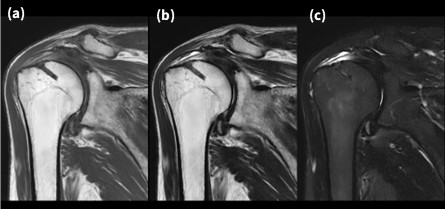

Fig.7-1に肩関節の画像を示す。PROPELLER MBを使用することで呼吸や体動によるモーションアーチファクトを抑制し8)、また高い磁場均一性を有していることからオフセンターにおいても均一な信号や脂肪抑制効果を発揮していることがわかる。また、PROPELLER MBはマルチショットにて1ブレードを収集できるため、ETLを増加させずブラーによるボケを抑制でき、TE延長を伴わないためT1WIやPDWIにも適用可能である。Fig.7-1に示す画像は全てPROPELLER MBで撮像を行っており、Cartesian法に比べ遜色ない画像と言える。

VoyagerMR30_ube12.jpg

Fig.7-1 PROPELLERとDLを併用した肩関節画像

(a) T1 FSE (b) T2 FSE (c) T2_STIR FSE

また、本症例はAIR MPコイルを使用しているため、前項で示したように高画質を提供できるほか、コイルが患部にやさしくフィットするため被検者の負担が少なく、ポジショニング時においても装置本体がワイドテーブルかつワイドボアのため、肩関節MRI検査は苦痛を伴わないやさしい検査となった。